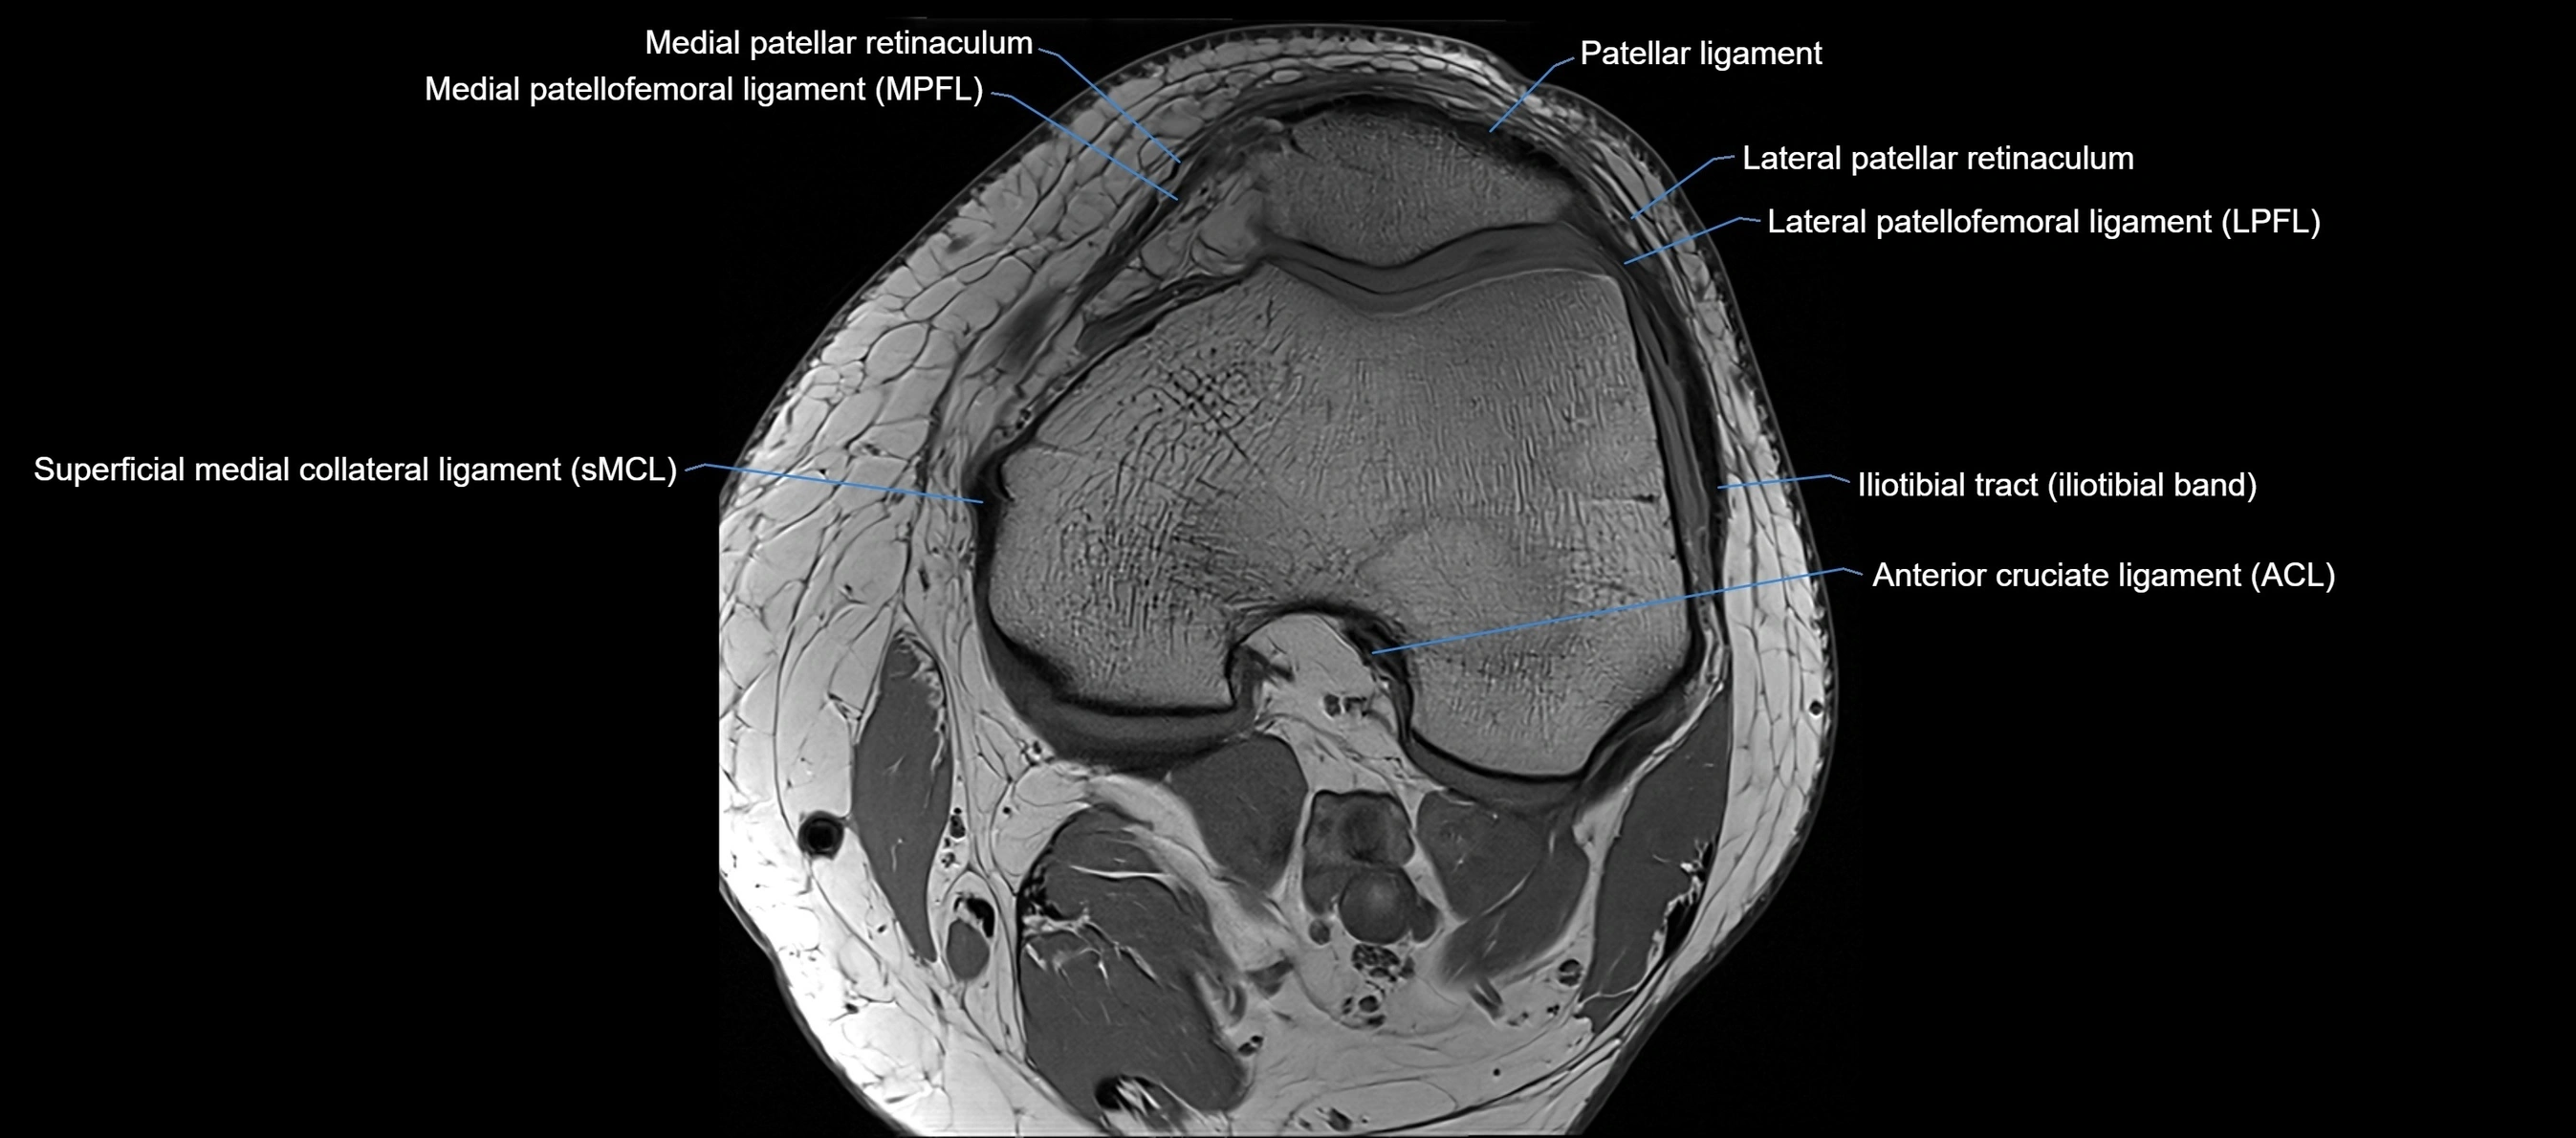

MRI images

image

MRI Appearance

T1-weighted images:

• Normal ACL appears as a low-signal band-like structure crossing the intercondylar notch

• Surrounded by intermediate signal synovial fluid and fat planes

T2-weighted images:

• Normal ACL remains low signal

• Partial or complete tears appear as discontinuity, increased signal, or fiber laxity